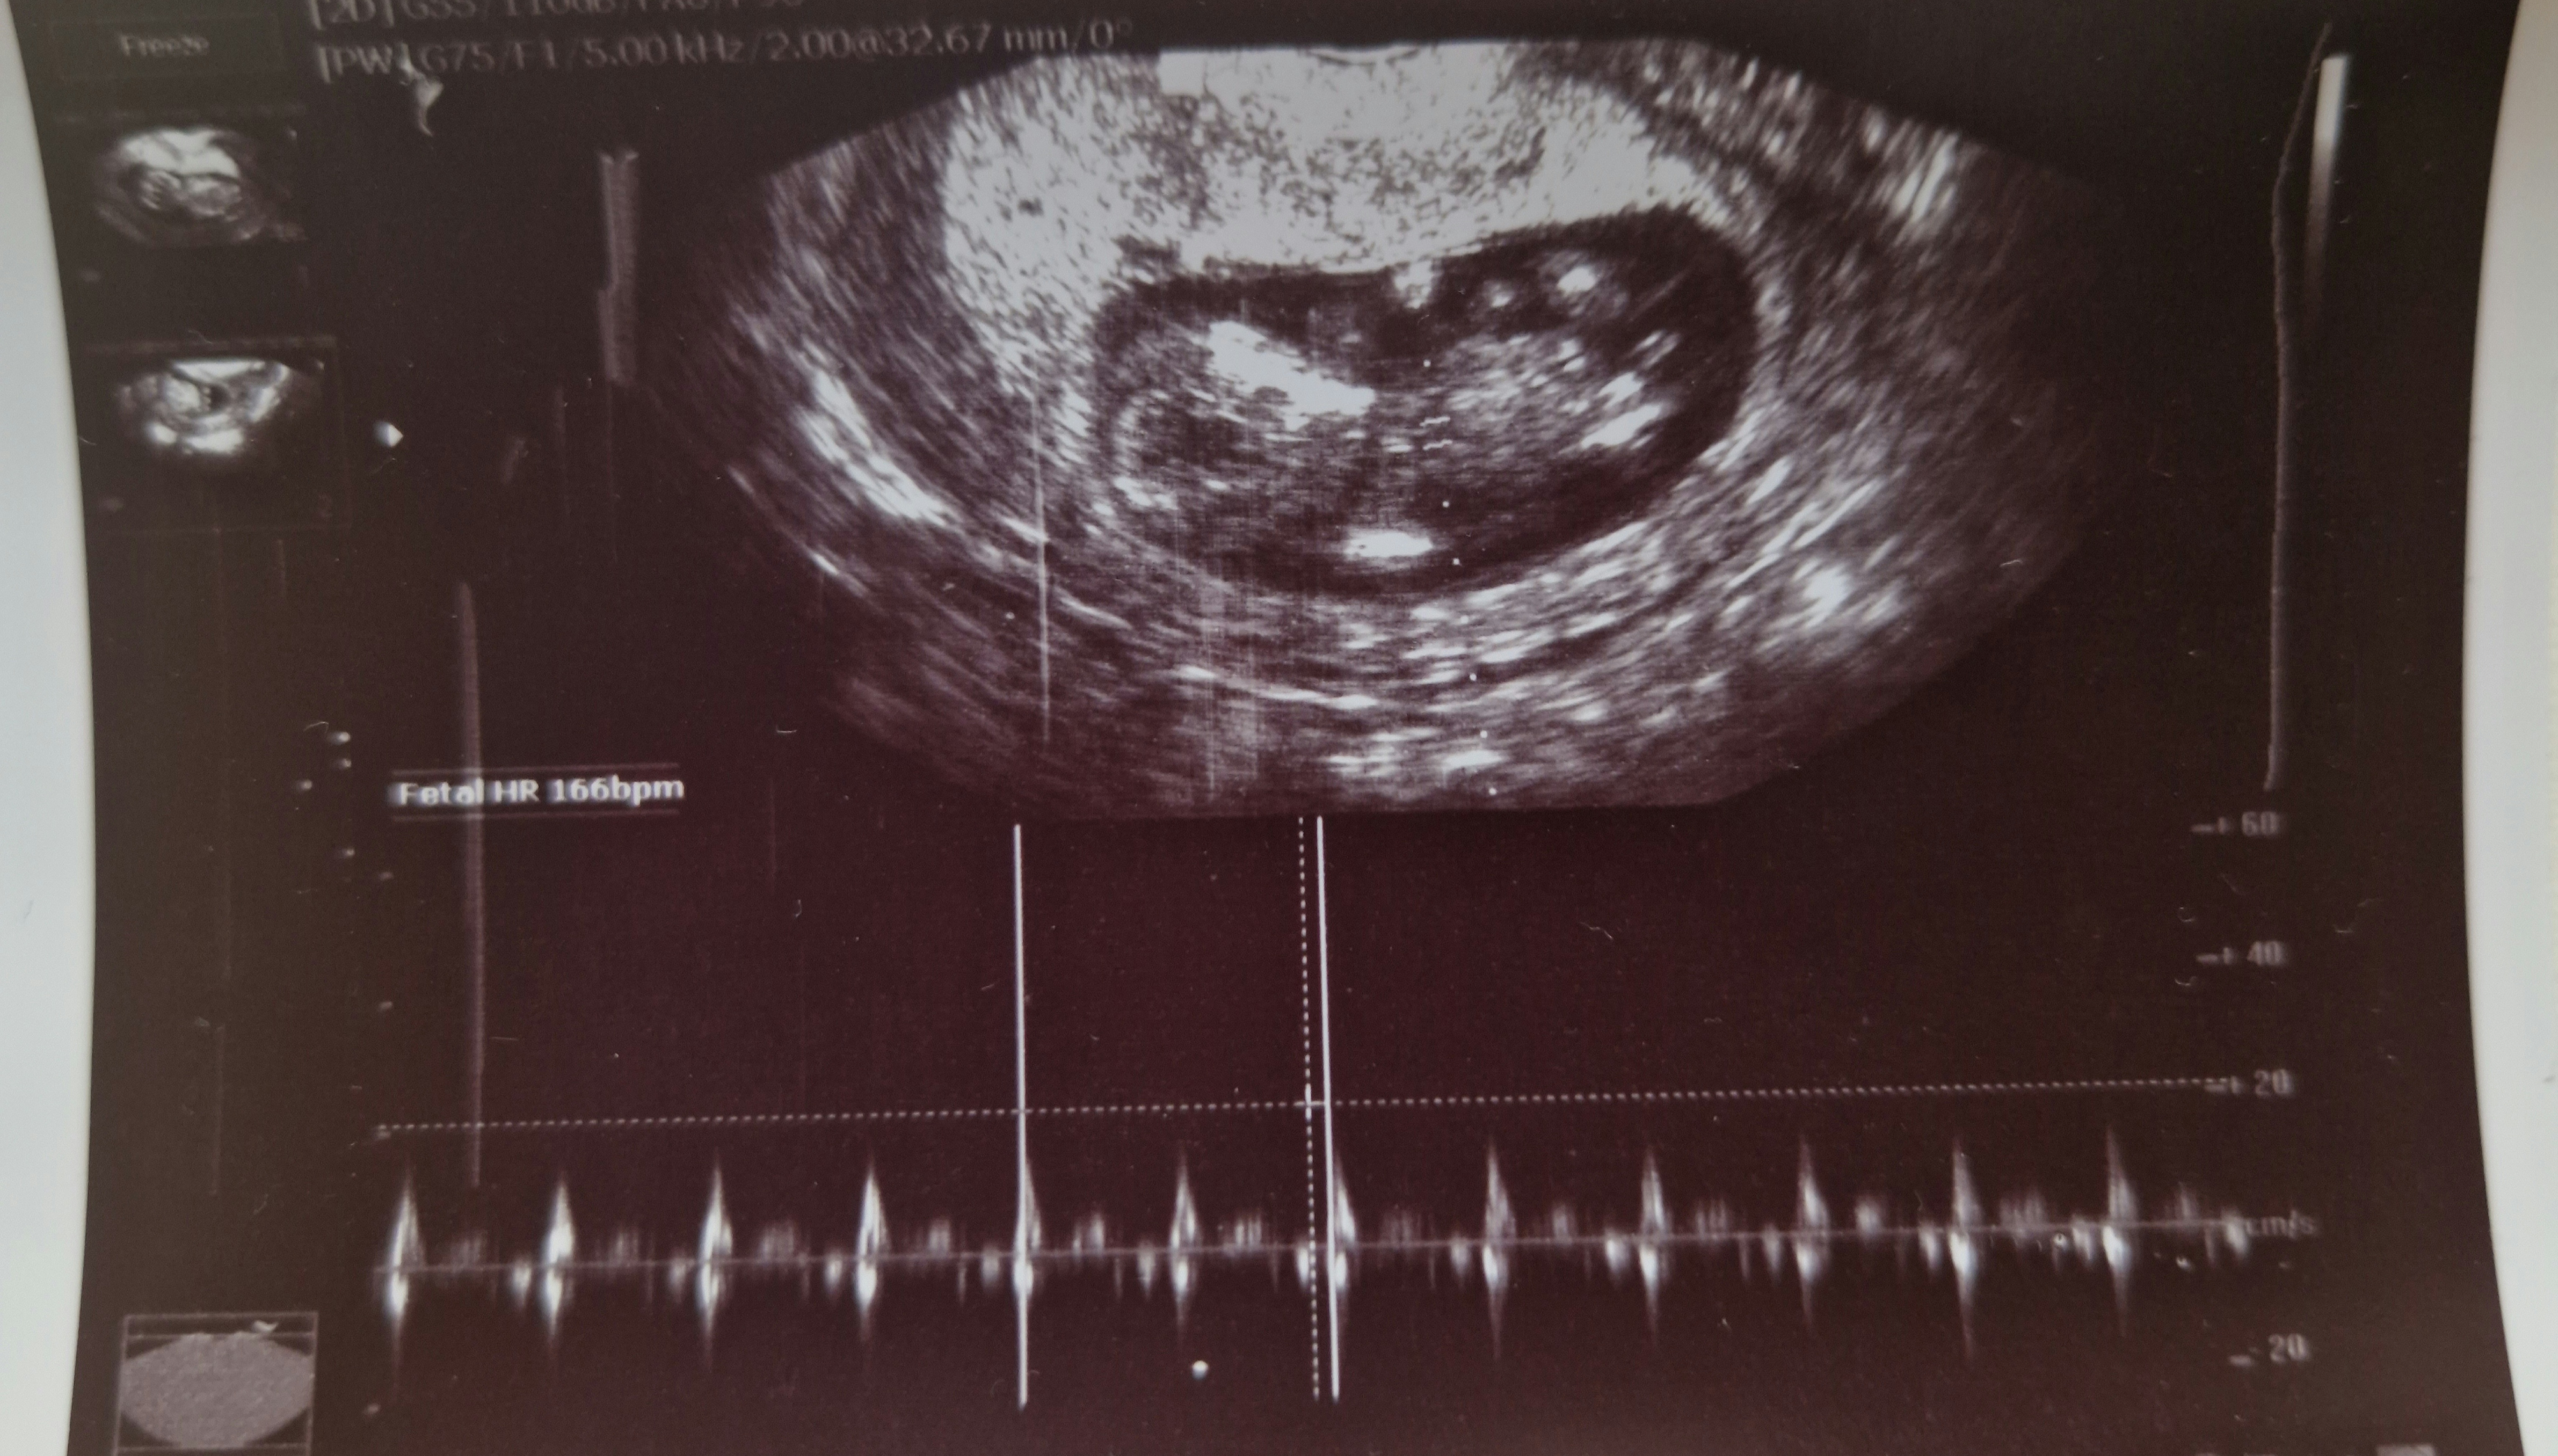

Mam jeszcze inne zdjecia z tej wizyty moze na nich cos widac (ja sie kompletnie na tym nie znam)